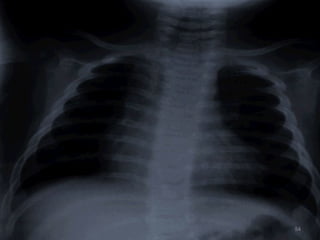

 CXR - Right. V & A enlargement

- Large pulm. artery

- ↑ed pulm. vascularity